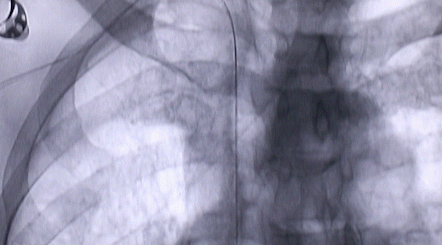

1月12日,西安國際醫(yī)學(xué)中心醫(yī)院心臟外科郭穎強(qiáng)主任團(tuán)隊(duì)成功為一名腹主動(dòng)脈閉塞、右側(cè)腎動(dòng)脈閉塞、左側(cè)腎動(dòng)脈重度狹窄、腹壁淺表動(dòng)脈側(cè)支循環(huán)形成、高血壓病3級(jí)(極高危組)合并閉塞性周圍動(dòng)脈粥樣硬化、急性腎功能不全的老年患者實(shí)施腎動(dòng)脈球囊擴(kuò)張 腎動(dòng)脈支架植入術(shù) 動(dòng)脈血栓抽吸術(shù) 髂動(dòng)脈開通術(shù),治好了困擾患者多年的頑固性高血壓。患者目前康復(fù)良好,將于近日出院。

按照術(shù)前制定的方案,郭穎強(qiáng)主任和楊金保博士首先嘗試開通閉塞的右腎動(dòng)脈,但由于血栓機(jī)化、鈣化嚴(yán)重,右腎動(dòng)脈難以開通。遂謹(jǐn)慎擴(kuò)張狹窄的左腎動(dòng)脈,并成功植入一枚支架。之后經(jīng)過反復(fù)旋磨、抽吸,順利開通髂動(dòng)脈,但腹主動(dòng)脈閉塞段仍難以擴(kuò)通。此時(shí),患者居高不下的血壓很快恢復(fù)到正常水平。

經(jīng)過3個(gè)半的奮戰(zhàn),最令張大伯頭疼的頑固性高血壓終于恢復(fù)了正常。術(shù)后當(dāng)日,張大伯便下床活動(dòng),次日復(fù)查腎功能,尿素氮、肌酐已基本恢復(fù)正常。